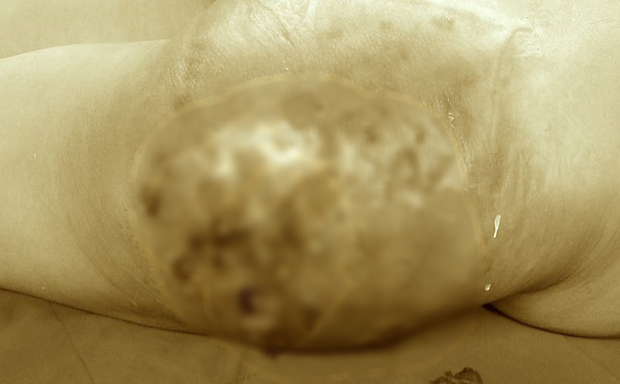

Nữ bệnh nhân bị hoại tử mông nghiêm trọng sau tiêm silicon

Nữ bệnh nhân 45 tuổi được chuyển đến Bệnh viện Trung ương quân đội 108 trong tình trạng vùng mông lở loét, hoại tử nghiêm trọng với diện tích khoảng 20 x 20 cm. Bệnh nhân cho biết do mông lép, chị mất tự tin khi mặc đồ nên đã quyết định đi bơm mông.

Tại Bệnh viện Trung ương quân đội 108, bệnh nhân được chẩn đoán bị hoại tử diện rộng da, mô mỡ vùng tiêm, viêm lan tỏa bẹn đùi. Bệnh nhân được mổ cấp cứu nạo vét ra khoảng 2.500 cc (khoảng 2,5 lít) tổ chức hoại tử và dịch mủ.